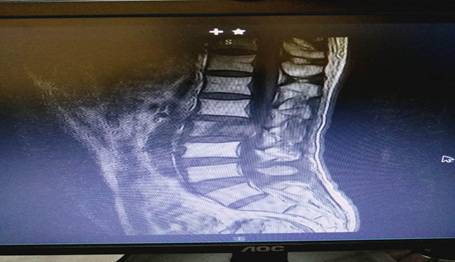

患者劉先生,54歲,患肝癌16個(gè)月,因腰腿痛伴下肢麻木4月余入住中心醫(yī)院脊柱外科。腰椎MRI顯示腰2椎體轉(zhuǎn)移腫瘤、椎管占位、神經(jīng)根受壓,PECT顯示腫瘤單節(jié)段椎體侵犯、椎弓根骨折。手術(shù)指針明顯。為最大限度地挽救患者的神經(jīng)功能,改善其生活質(zhì)量,脊柱外科決定為其施行手術(shù)切除減壓。術(shù)前,蘇光輝、汪向東二位主任帶領(lǐng)科室技術(shù)骨干與腫瘤科尹忠文主任、血管外科涂宏主任、麻醉科段雪琴主任多次會(huì)商術(shù)前計(jì)劃,經(jīng)周密術(shù)前準(zhǔn)備后,術(shù)前當(dāng)天由血管外科先行瘤體血管栓塞術(shù),以減少術(shù)中出血,栓塞手術(shù)非常成功,手術(shù)按時(shí)進(jìn)行。術(shù)中蘇光輝主任、汪向東副主任與肖華斌、陳威副主任醫(yī)師為其施行腫瘤椎體全切術(shù)。術(shù)中出血量在2000ml以內(nèi),出血量的控制超出手術(shù)團(tuán)隊(duì)的預(yù)期。手術(shù)相當(dāng)順利,術(shù)后患者快速康復(fù)出院。

術(shù)前腰椎MRI 圖片